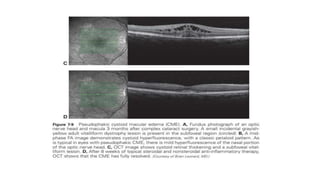

Cystoid Macular Edema

• Cystoid macular edema (CME) is characterized by intraretinal edema

contained in honeycomb-like cystoid spaces.

• The source of the edema is abnormal perifoveal retinal capillary

permeability

• FA shows multiple small focal leaks and late pooling of the dye in

extracellular cystoid spaces.

• OCT shows diffuse retinal thickening with cystoid areas that are more

prominent in the inner nuclear and outer plexiform layers.

• A non reflective cavity that is consistent with subretinal fluid

accumulation is present beneath the neurosensory retina.

• Pooling classically forms a “flower petal.

• Ocular surgery-cataract surgery=Irvine Gass syndrome

• pseudophakic CME